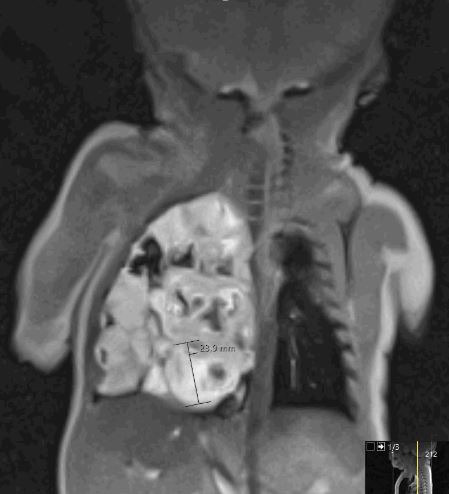

2. Magnetresonanztomografie (MRT): Wenn die Ultraschallbilder nicht eindeutig sind oder eine detailliertere Darstellung erforderlich ist, kann in unserer Klinik eine fetale MRT durchgeführt werden. Diese Technik bietet präzisere Bilder der fetalen Lunge und kann helfen, CPAM von anderen möglichen Lungenanomalien zu unterscheiden.

- Magnetresonanztomografie (MRT) der Brust: Ein MRT-Scan bietet detaillierte Bilder der Lunge und kann genutzt werden, um die Struktur der CPAM und ihre Beziehung zu anderen Lungenbereichen zu verstehen. Sie benötigt keine für das Kind belastende Röntgenstrahlung